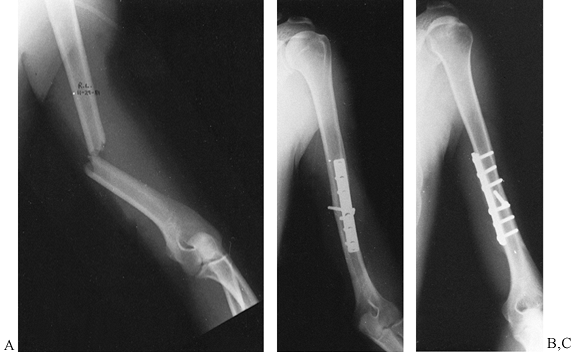

If an open reduction is performed, a small clover-leaf plate, modified

clover-leaf plate (35), or a blade plate (66) (Fig. 15.28)

can be used to fix the fracture. In osteopenic bone, however, plates

and screws should be avoided because of the risk of hardware pullout

and failure. Ender’s nails with a figure-of-eight tension band

neutralize rotational and translational forces and provide adequate

fixation to allow early ROM (Fig. 15.29).

Tension band suturing or wiring alone usually do not provide fixation

rigid enough to allow early ROM in patients with osteoporosis.

![]() |

|

Figure 15.28. A:

Preoperative AP radiograph of a two-part surgical neck proximal humerus fracture. Note that although the greater tuberosity is fractured, it is not displaced and therefore not considered a displaced “part.” B: Scapular lateral view of fracture. C: Postoperative AP radiograph showing reduction and fixation with a 4.5 reconstruction plate fashioned into a “blade” plate. The patient also had a #5 nonabsorbable suture placed in a figure-of-eight tension band, which cannot be visualized. D: Postoperative axillary view of fracture fixation. |